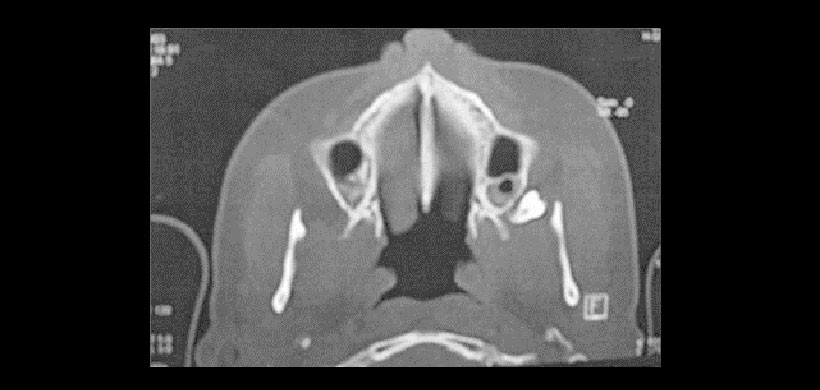

Fig 3. La tomografía volumétrica se debe considerar como una última alternativa y siempre y cuando los exámenes radiográficos convencionales en 2 D no brinden la suficiente información Por ejemplo en la imagen se observa a la pieza 2.8 desplazada cefálicamente en un intento de exodoncia, se corrobora esta posición de la pieza con una Tomografía Computarizada en corte horizontal, y se estudia la posición ántero posterior.